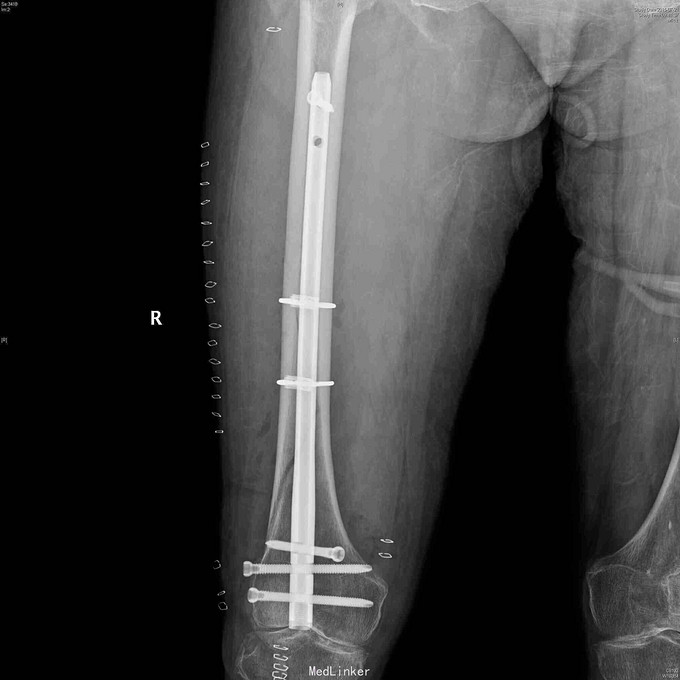

诊断:右股骨干骨折。 治疗:先行下肢牵引,排除血管神经损伤后,行股骨干中下段螺旋骨折倒打髓内钉技术治疗,术中先行股外侧入路切开用钢丝捆扎复位固定骨折,再穿钉。术后定期拍片复查,预防骨质疏松治疗。

随防:三个月后复诊,患者一般情况好,右大腿无肿痛,右膝可屈至100度。建议继续扶拐行走,并继续预防骨质疏松治疗。 讨论:本例为股骨干中下段长螺旋骨折,骨折线长,若行钢板固定,手术创伤大,软组织剥离多,骨折愈合慢,故选用了倒打髓内钉技术治疗,骨膜剥离少,骨折不愈合可能性小。但倒打钉经膝关节髁间入路,损伤关节面,技术要求高,对膝关节屈伸功能有一定影响,手术指征应严格把握。一起交流一下股骨骨折钢板固定和髓内钉固定的选择方面有何经验和技巧?